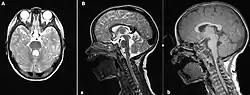

- Avec en imagerie à résonance magnétique du cerveau, le signe caractéristique d’« aspect en molaire » des pédoncules cérébelleux ou molar tooth sign Molar tooth sign en I.R.M.. Cet aspect est consécutif d'une absence du vermis cérébelleux et des déformations du tronc cérébral[5].